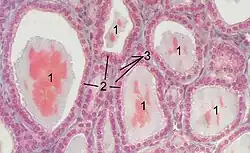

No nível microscópico, existem três características principais da tireoide - folículos, células foliculares e células parafoliculares, descobertas pela primeira vez por Geoffery Websterson em 1664.[15]

- Folículos

Os folículos da tireoide são pequenos agrupamentos esféricos de células de 0,02 a 0,9 mm de diâmetro que desempenham o papel principal na função da tireoide.[5] Eles consistem em uma borda que tem um rico suprimento de sangue, presença de nervos e linfáticos, que envolve um núcleo de colóide que consiste principalmente de proteínas precursoras do hormônio tireoidiano chamadas tireoglobulina, uma glicoproteína iodada.[5][16]

- Células foliculares

O núcleo de um folículo é circundado por uma única camada de células foliculares. Quando estimulados pelo hormônio estimulador da tireoide (TSH), eles secretam os hormônios da tireoide T3 e T4. Eles fazem isso transportando e metabolizando a tireoglobulina contida no colóide.[5] As células foliculares variam em forma de planas a cubóides a colunares, dependendo de quão ativas são.[5][16]

- Células parafoliculares

Espalhadas entre as células foliculares e em espaços entre os folículos esféricos estão outro tipo de célula tireoidiana, as células parafoliculares.[5] Essas células secretam calcitonina e, portanto, também são chamadas de células C.[17]